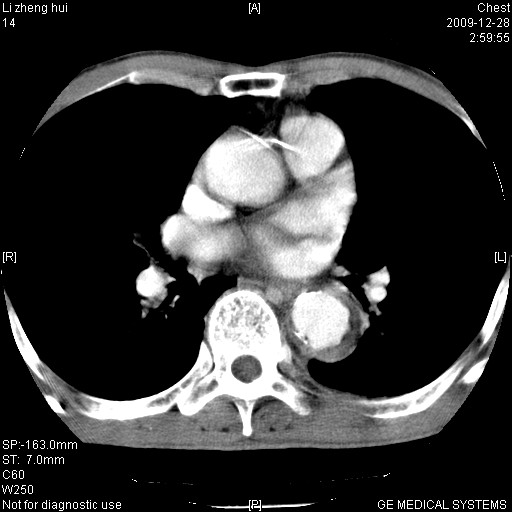

标题: CT23859:胸主动脉瘤

男  79岁 胸部痛急诊入院,晚上做的增强

考虑主动脉瘤?(增粗、钙化、壁血栓?)

支持降主动脉瘤,不考虑夹层

动脉瘤伴附壁血栓

1)考虑胸主动脉壁间血肿或夹层动脉瘤。2)多发性肝囊肿。

1)考虑胸主动脉附壁血栓或夹层动脉瘤。2)多发性肝囊肿。